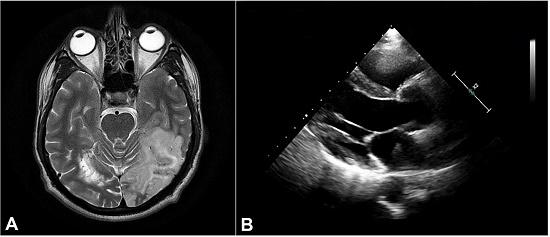

Non-contrasted computed tomography (NCCT) of the brain revealed an acute ischemic infarct in left Middle Cerebral Artery (MCA) -Posterior cerebral artery (PCA) watershed areas and distal MCA region along with multiple old lacunar infarcts (Figure 1A). His biochemical parameters remained normal except for a rise in ESR (Erythrocyte Sedimentation Rate, Normal Value ≤ 15 mm/hr) to 30 mm/hr within 3 days. The patient was managed as a case of Stroke in Young. As multiple infarcts on NCCT indicated a thromboembolic phenomenon, a TEE was done to rule out any cardiac cause. On TEE, a left atrial (LA) mass measuring 2.93 cm2, mobile, attached to the interatrial septum (IAS) near the Inferior Vena Cava (IVC) junction was noted with suspicion of atrial myxoma (Figure 1B).